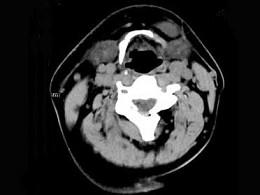

问题 男,32岁,左侧下颌部肿块,CT如图所示,最可能的诊断是 ( )

选项 A、颈部淋巴管瘤 B、舌下腺囊肿 C、颌骨囊肿 D、鳃裂囊肿 E、造釉细胞瘤

答案 B